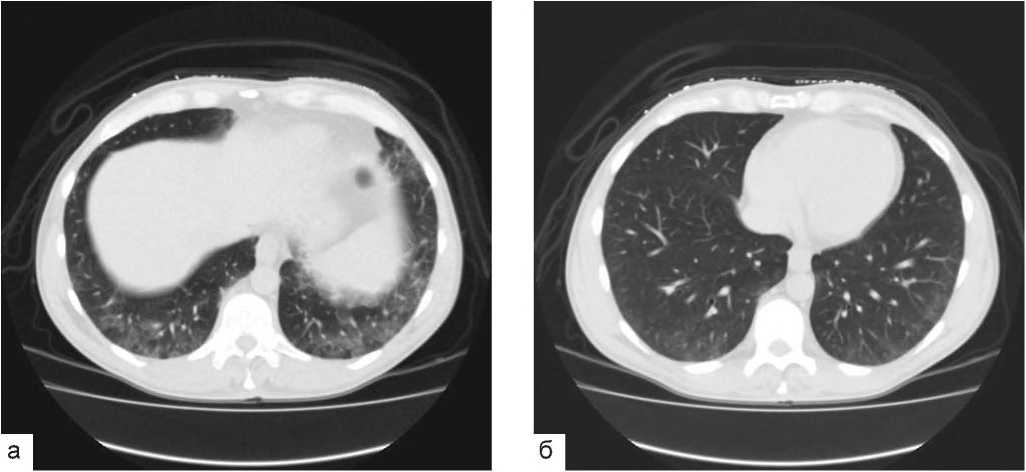

Инструментальные исследования выявили следующее. Компьютерная томография (КТ) органов грудной клетки: двусторонние интерстициальные изменения в легких («матовое стекло», утолщение междольковых перегородок) (рис. 1а, б).

Рис. 1.

КТ органов грудной клетки. Аксиальные срезы. В нижних отделах легких, в основном а базальных сегментах нижних долей, выявляются довольно обширные зоны пониженной воздушности по типу "матового стекла", на фоне которых видны умеренные интерстициальные ретикулярные изменения, обусловленные утолщением междольковых и внутридольковых перегородок. Обращает внимание преимущественная вовлеченность в процесс кортикальных и субкортикальных отделов легких.